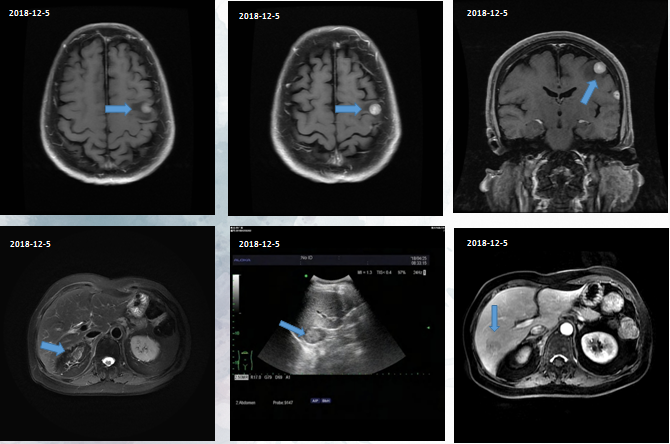

影像阳性检查

影像学检查:

乳腺核磁、淋巴结超声、骨扫描等均未见异常。

脑转移

肝转移

时隔1个月,患者的头颅MR检查提示明显进展,病灶增多、增大。

小脑的病灶也在增大,肝脏病灶轻微的增大,右侧肾上腺转移也明显增大。